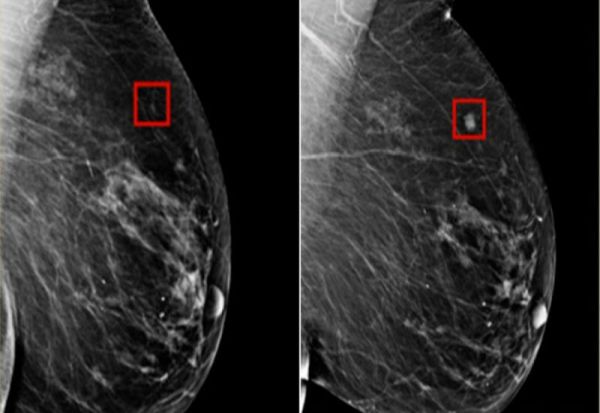

Вештачка интелигенција успеала да детектира рак на дојка четири години пред да се развие

Истражувачите од Институтот за технологија во Масачусетс развиле систем кој користи вештачка интелигенција за да помогне во предвидувањето на идниот ризик од развој на рак на дојка.

- Овој систем идентификува ризик. Може да ѝ каже на жената дека е изложена на висок ризик за развој на рак на дојка пред уште да се развие ракот на дојка - вели д-р Нортон.